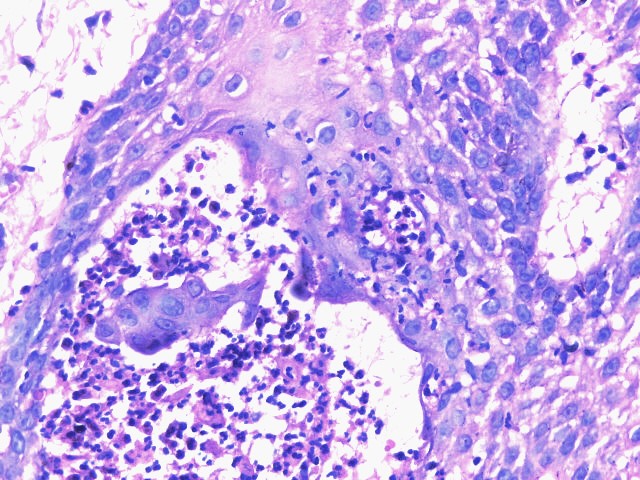

El pénfigo vegetante, es una variante rara del pénfigo vulgar (PV) corresponde a 1-2 % de los casos, las características clínicas e histopatológicas habitualmente permiten la diferenciación en 2 subtipos descritos: Neumann y Hallopeau, pero en ocasiones pueden presentarse de forma simultánea o secuencial. Las lesiones adoptan un aspecto vegetante afectando cualquier área de la piel, pero predomina en áreas intertriginosas y mucosa oral. Presentamos el caso de una paciente de 31 años de edad, con 1 año de evolución de placas eritematosas con vesículas y pústulas en la superficie cutánea, simulando dermatosis eccematosas que no permitían realizar el diagnóstico. Luego de la suspensión del tratamiento con esteroides sistémicos que recibía, se logró establecer el diagnóstico definitivo al evidenciar las características clínicas del pénfigo vegetante y corroborar con el estudio histológico e inmunofluorescencia directa.

Pemphigus vegetans, is a rare variant of pemphigus vulgaris (PV) corresponding to 1-2% of cases, clinical and histopathological characteristics usually allow the differentiation into 2 described subtypes: Neumann and Hallopeau, but sometimes they can present simultaneously or sequentially. Lesions adopt a vegetative appearance, affecting any area of the skin, but predominate in intertriginous areas and oral mucosa. We present the case of a 31-year-old female, who presented clinical manifestations of both variants, making their differentiation impossible, simulating eccematous dermatosis. After suspension of systemic steroids, final diagnosis was made based on clinical, histologic and direct immunofluorescence studies.